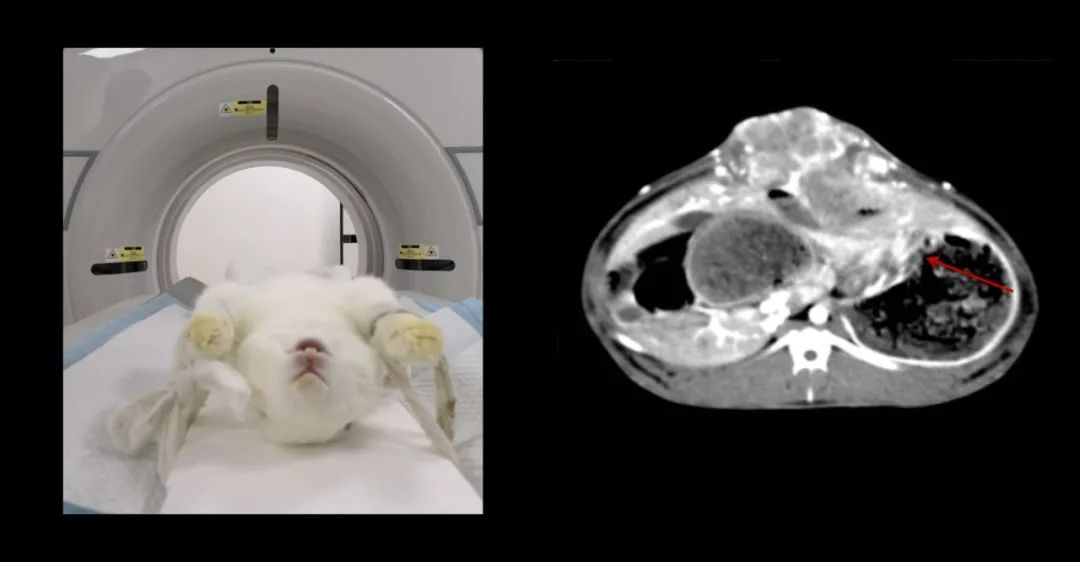

明峰醫療CT下的寵物世界

你養寵物嗎?如今,越來越多的人,通過飼養寵物,為生活增添一份別樣的色彩。這些可愛的小家伙們成為了人類的朋友。

不過,寵物也會生病,也會頭痛發熱,也會上吐下瀉。有時需要通過CT掃描來診斷病情,CT不但可以看到寵物的內部組織和器官,也可以顯示各種微小的病變。在寵物可愛美麗的外表下,它們的CT掃描圖像是什么樣子呢?

一直以來,明峰醫療作為醫療影像產業鏈綜合解決方案提供商,始終堅持在影像領域深耕和探索,也擁有出色的寵物CT產品及臨床應用案例。

7歲,38kg的金毛狗近期總是嘔吐,CT全身平掃+增強,發現肝和胃占位性病變。